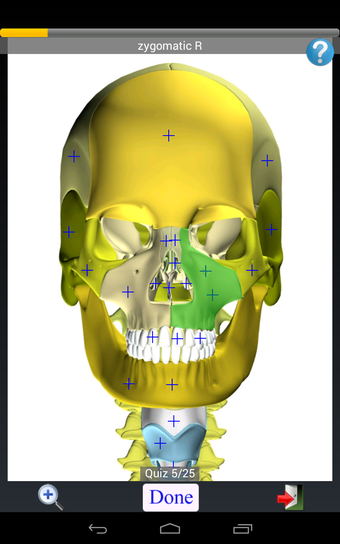

Anatomy Quiz Free es una aplicación de Android de Education Mobile que ofrece una amplia gama de cuestionarios para ayudar a los usuarios a aprender anatomía humana. La aplicación cuenta con más de 500 cuestionarios que ponen a prueba tu capacidad para identificar la ubicación correcta de un objeto dado su nombre. Los cuestionarios se generan a partir de modelos de anatomía 3D virtuales, lo que los hace más atractivos e interactivos. La aplicación es gratuita y no hay versiones premium ni compras dentro de la aplicación.

La aplicación es compatible con los idiomas inglés, francés, español y alemán, lo que la hace accesible para usuarios de diferentes partes del mundo. Las imágenes de alta resolución son nítidas y claras, y la función de zoom con pellizco te permite acercar y alejar las imágenes para una mejor vista. El cuestionario de posición viene con un temporizador, lo que lo hace más desafiante y emocionante. Además, la aplicación tiene una función de transferencia a la tarjeta SD, lo que facilita su transferencia a otros dispositivos.